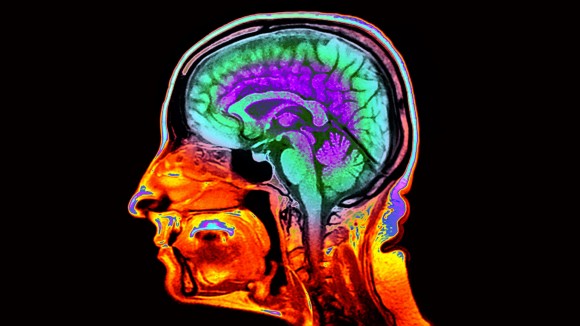

Citra Otak MRI Ungkap Kecepatan Penuaan dan Risiko Penurunan Memori

Durham, Amerika Serikat - Para ilmuwan telah menemukan cara baru untuk mengetahui seberapa cepat otak seseorang mengalami penuaan dengan menggunakan gambar MRI. Dengan melihat ketebalan dan volume bagian otak tertentu, mereka bisa memprediksi risiko penurunan ingatan dan kemampuan berpikir.

Penelitian ini melibatkan lebih dari 50.000 gambar otak dan menggunakan algoritma komputer untuk menghubungkan ciri-ciri otak dengan data kesehatan dan fungsi tubuh dari ribuan orang yang telah dipantau sejak lahir.

Jam penuaan berbasis MRI ini memberikan keuntungan dibandingkan pemeriksaan darah biasa karena bisa melihat struktur otak langsung, yang membantu memahami bagaimana perubahan fisik memengaruhi fungsi otak.